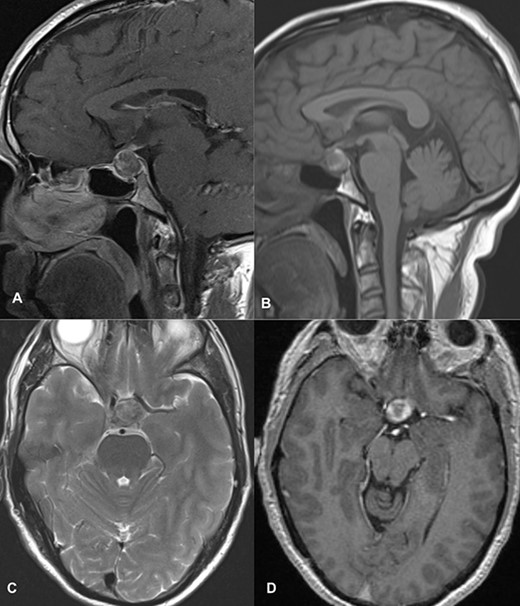

Magnetic resonance imaging (MRI) (axial T1, axial T2, coronal T1 and sagittal T1-weighted images) revealed a sellar and suprasellar lesion measuring 3 × 2.9 × 1.8 cm with patchy areas of high signal on T1-weighted images and signal void on T2-weighted images suggestive of hemorrhage. The suprasellar component of the lesion was displacing optic chiasma superiorly and the sellar component was causing sellar expansion with mass effect on bilateral cavernous sinuses (left>right); right internal carotid artery (ICA) had a contact angle of 90°, whereas left ICA had >90° (Fig. 1).

MRI images of axial T1 (A), axial T2 (B), coronal T1 (C), and sagittal T1-weighted images (D) showing a 3 cm × 2.9 cm × 1.8 cm sized suprasellar lesion displacing optic chiasma superiorly and laterally causing a mass effect on bilateral cavernous sinuses (Left>Right) with patchy areas of high signal on T1-weighted images and signal void on T2-weighted images suggestive of hemorrhage.